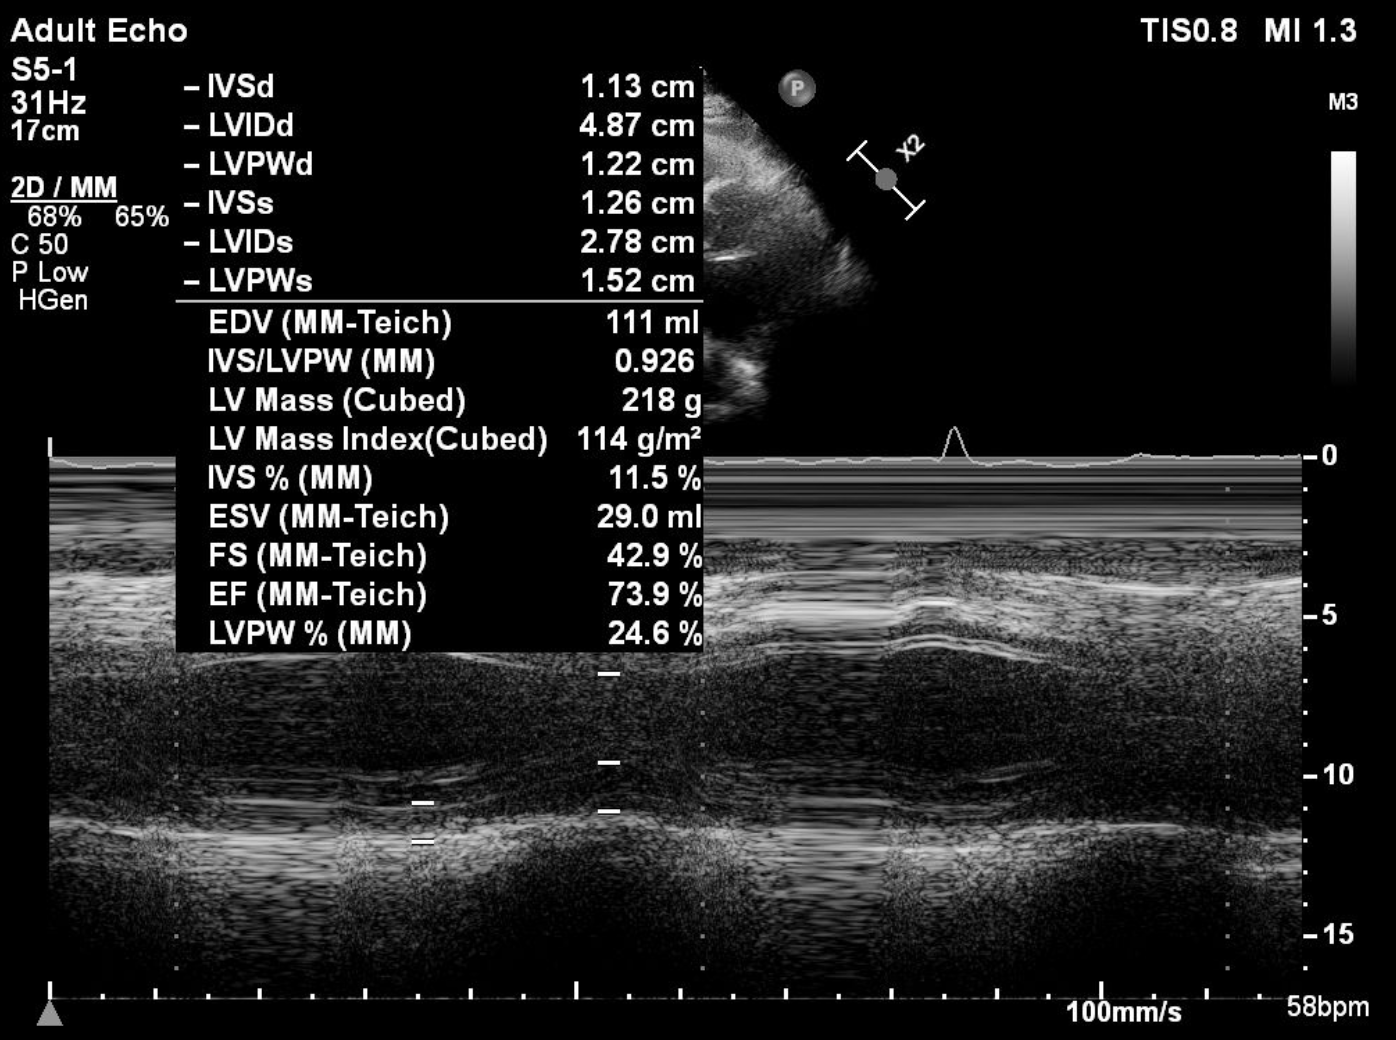

Resting ECG was normal. Referring hospital¡¯s treadmill test showed positive ischemic response with high-risk Duke score. Echocardiography showed preserved ejection fraction.

Angiography showed small non-dominant RCA with proximal severe stenosis, Left Main with severe tubular calcified stenosis at distal segmen, bifurcation lesion (medina1-1-1), LAD with diffuse calcified subtotal stenosis from ostial–mid, and LCX iwth severe tubular calcified stenosis at ostial.